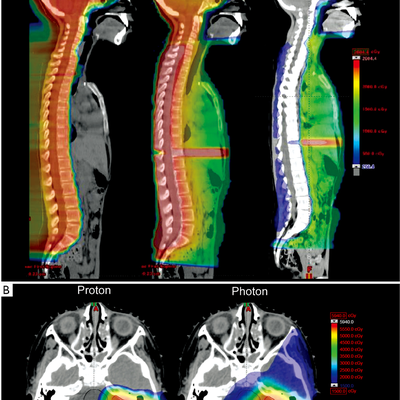

Radiothérapie - Proton contre photon : une autre lutte

Notre radiothérapeute de lyon, dr. c nous a toujours expliqué qu'il n'y aurait pas de bénéfice pour notre fils à recevoir de la proton thérapie. pour nous convaincre, elle a même contacté dr. a. de l'institut curie (seul centre proposant de la proton thérapie en france) pour lui demander si notre fils âgé de 3 ans aurait un quelconque b

Protonthérapie à Orsay pour les médulloblastomes: oui mais pas pour tous

J'ai envoyé à dr. h de l'institut curie la petite revue de littérature que j'ai déjà publiée dans "radiothérapie - pronton vs photon: une autre lutte". je lui demande donc d'étudier notre demande de protonthérapie pour notre fils. elle me répond qu'après l'appel du dr. d. de l'hôpital poincaré de garches, elle s'est apperçue que le do